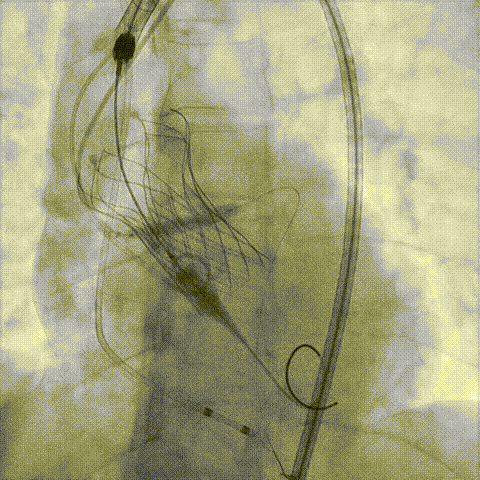

冠脉造影

手术策略和器械选择

预置Telescope™导引延长导管及导丝保护左冠,

18mm球囊预扩张再次评估冠脉闭塞风险。

介入经过及结果

Telescope™+Runthrough

18mm*40mm 预扩张

预埋 Resolute Integrity 3.5*26mm

再次评估左冠开口

第一次释放

再次评估左冠开口,考虑调整瓣膜深度

回收后调整深度,再次释放

评估左冠开口

左冠开口切线位造影

决定左冠烟囱支架保护冠脉

调整支架位置

释放冠脉支架

释放瓣膜

造影评估

支架内后扩张

根部造影